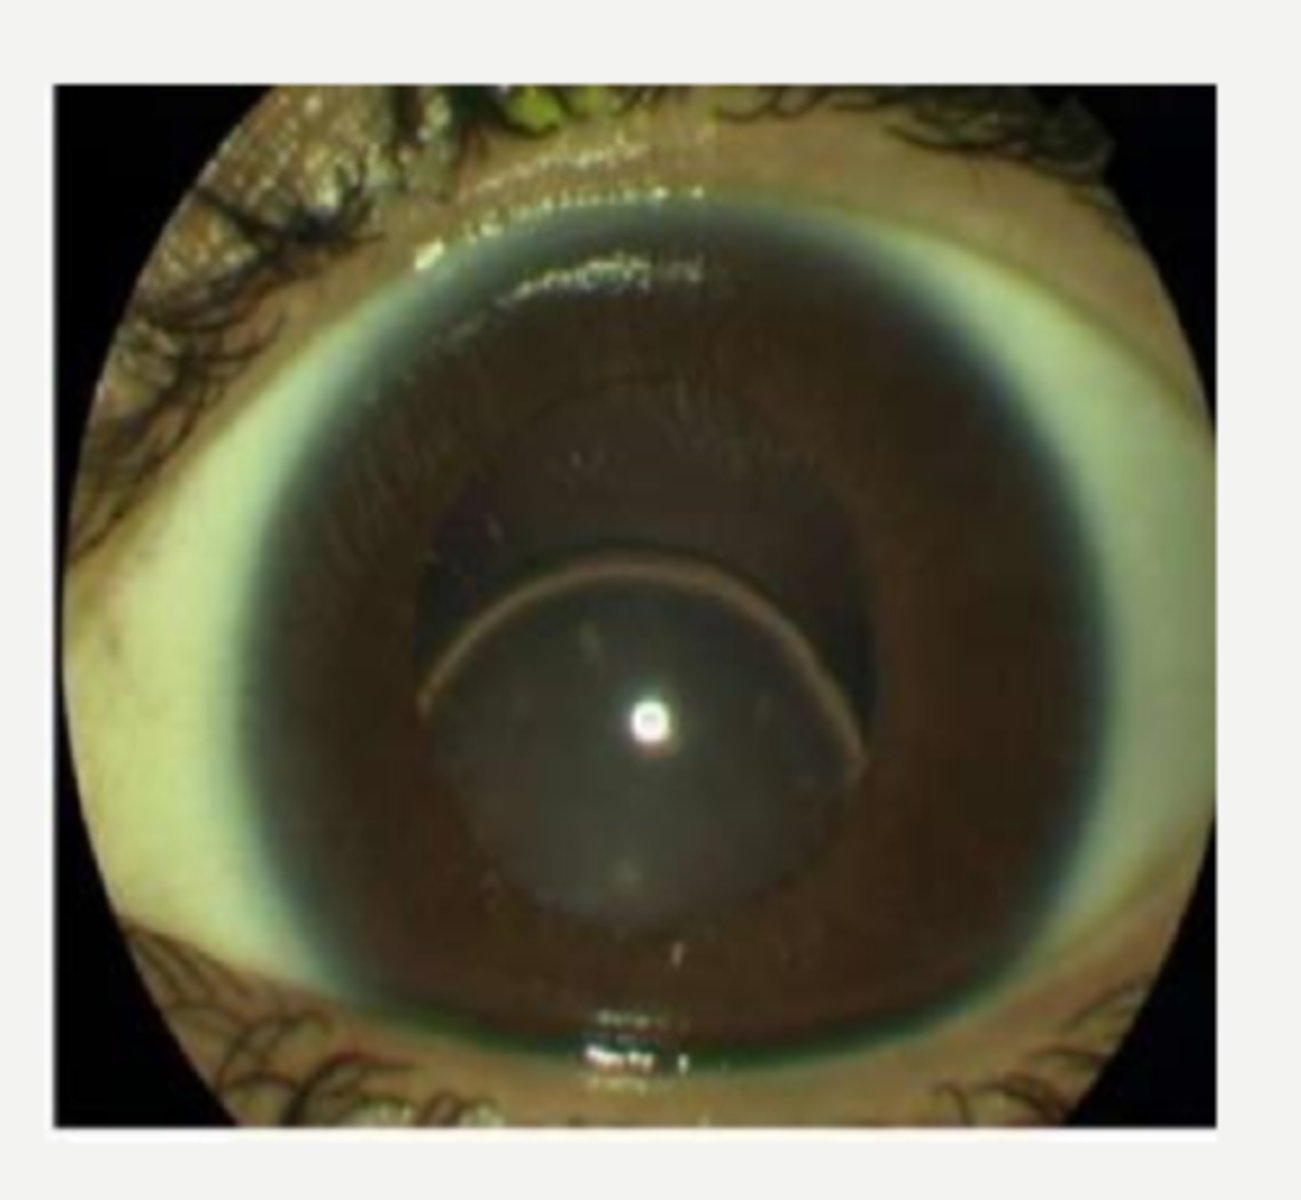

What is asteroid hyalosis?

unilateral

Is asteroid hyalosis usually unilateral or bilateral?

no = typically asymptomatic, though pt MAY complain of floaters

Does asteroid hyalosis typically affect vision?

these are adherent to the vitreous framework, so they stay suspended with ocular movement

How can we differentiate asteroid hyalosis from synchisis scintillans, a similar DDx?